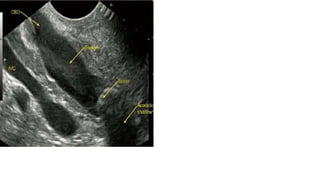

TRANSABDOMINAL ULTRASONOGRAPHY

• Ultrasound of abdomen is an extremely useful and accurate method for identifying gall stones and

pathologic changes in gall bladder consistent with acute cholecystitis .

• Abdominal ultrasound ,if performed by an experienced operator , should be part of the routine

evaluation of patients suspected of having gall stone disease , given the high specificity ( > 98 %) and

sensitivity ( >95%) of this test for the diagnosis of cholelithiasis .

• In addition to identifying gall stones , ultrasound can also detail signs of cholecystitis such as thickening

of gall bladder wall , pericholecystic fluid , and impacted stone in the neck of gall bladder .

• It is often the initial screening test for patients with suspected extrahepatic biliary obstruction

• Dilation of extrahepatic ( >10mm) or intrahepatic ( >4mm) bile ducts suggests biliary obstruction

• Intraoperative ultrasound is now used frequently to further evaluate intrahepatic lesions , assess

resectability , and determine involvement of vascular structures